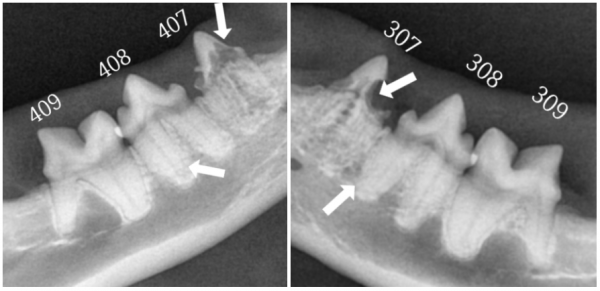

dda74ec2cbe3c1a8b77df26586ebe9fb_1765777801_1516.png

→ 우측·좌측 하악 어금니

407,408 치아흡수성병변

307,308 치아흡수성병변

치아흡수성병변이 확인된 치아는

이미 손상된 치질이 회복되지 않기 때문에

발치를 통해 통증의 원인을 제거해야 합니다.